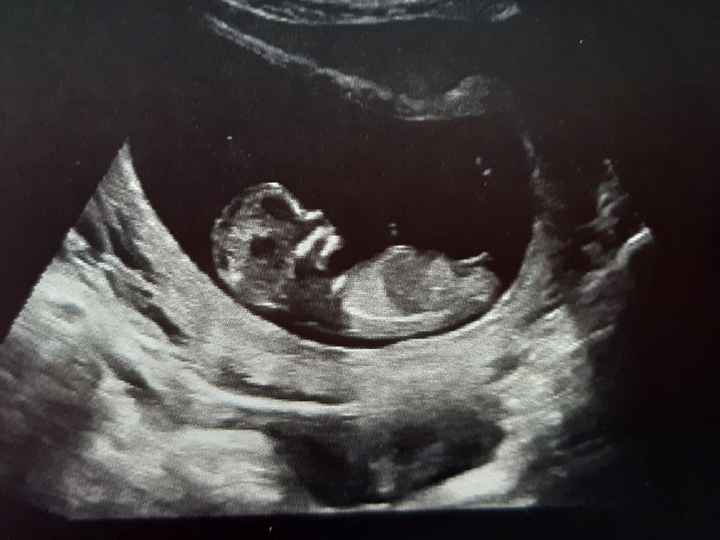

Oggi ho fatto la traslucenza nucale e la dottoressa mi ha detto che il fagiolino era in posizione impeccabile,tanto che il tubercolo si vedeva benissimo e mi ha detto femmina al 100%. Io già da ramzi avevo predetto femmina, ma aspettavo di snetirmelo dire. E così, com'è stato per il primo figlio dove secondo ramzi era maschio, e maschio è stato, anche stavolta ci ha preso 😍 siamo felicissimi, la bimba sta alla grande e si chiamerà VITTORIA. 🌺🌺🌺🌸🌸 Vi lascio l'eco di oggi dove si vede benissimo il tubercolo parallelo alla spina dorsale. Un bacio